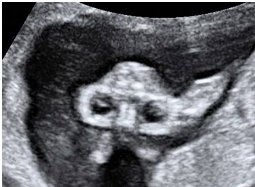

【110-1 醫學(六) 第56題】

36歲孕婦,G5P2SA1AA1,妊娠16週,接受超音波檢查,結果如圖所示: 則胎兒異常器官名稱與特徵(sign)為何?